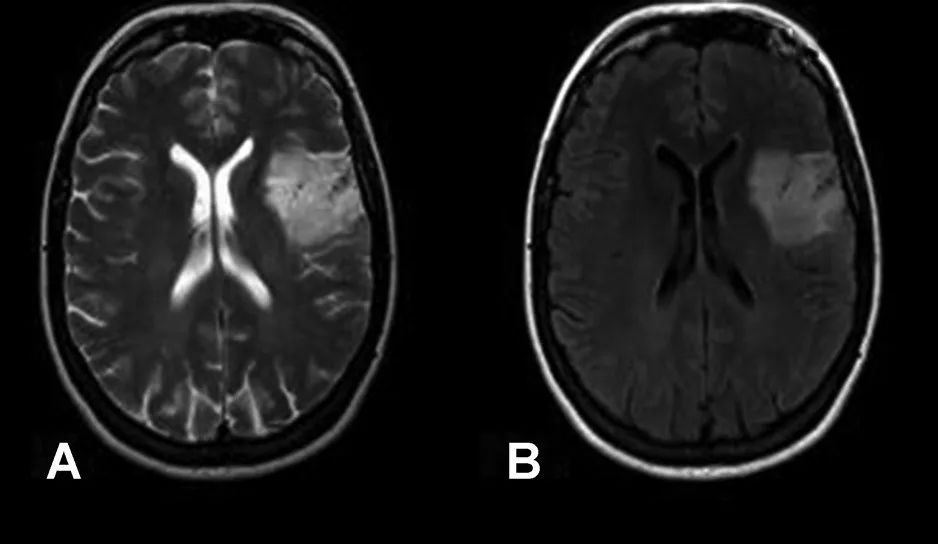

尽管肿瘤相对于 T2WI 在 FLAIR 序列上包含小的低信号区域(箭头),但大部分占位在 FLAIR 上显示的信号类似于 T2WI,不符合 T2-FLAIR 错配

肿瘤 T2WI 高信号不均质,不符合 T2-FLAIR 错配